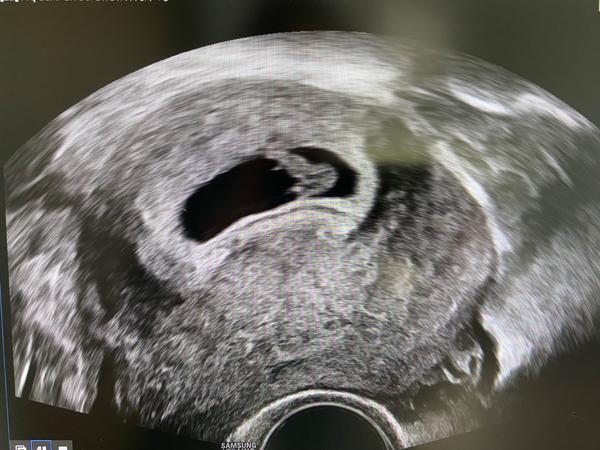

Zobák na ultrazvuku. Co to znamená?

Ahojky, kdyz mi dotkorka rikala, co co znamena. Tak jsem neposlouchala a byla v udivu😀ted ale koukam, a proc to vypada, ze ma na obliceji zobak?😆Co to muze byt? Vyzna se nekdo v ultrazvuku? Nechci tam furt videt ptacka😂

Je to embryo to jeste nemá ani snad prsty na tož nos 😆 prostě mini mimi